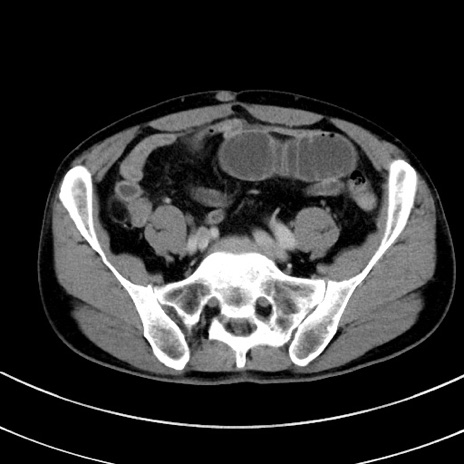

症例8(横断像)

【症例】 60歳代男性

【主訴】 黒色吐物

【現病歴】 4日前から嘔気自覚、2日前の朝食後にも嘔気あり、自分で手で嘔吐反射起こし嘔吐したところ血が混ざっていたため受診。

【既往歴】 5年前汎発性腹膜炎を伴う急性虫垂炎で手術、高血圧、前立腺肥大症、高脂血症

【身体所見】 腹部正中に手術癩痕あり 腹部平坦・軟圧痛なし膨満感あり

【データ】WBC 8400、CRP 4.54